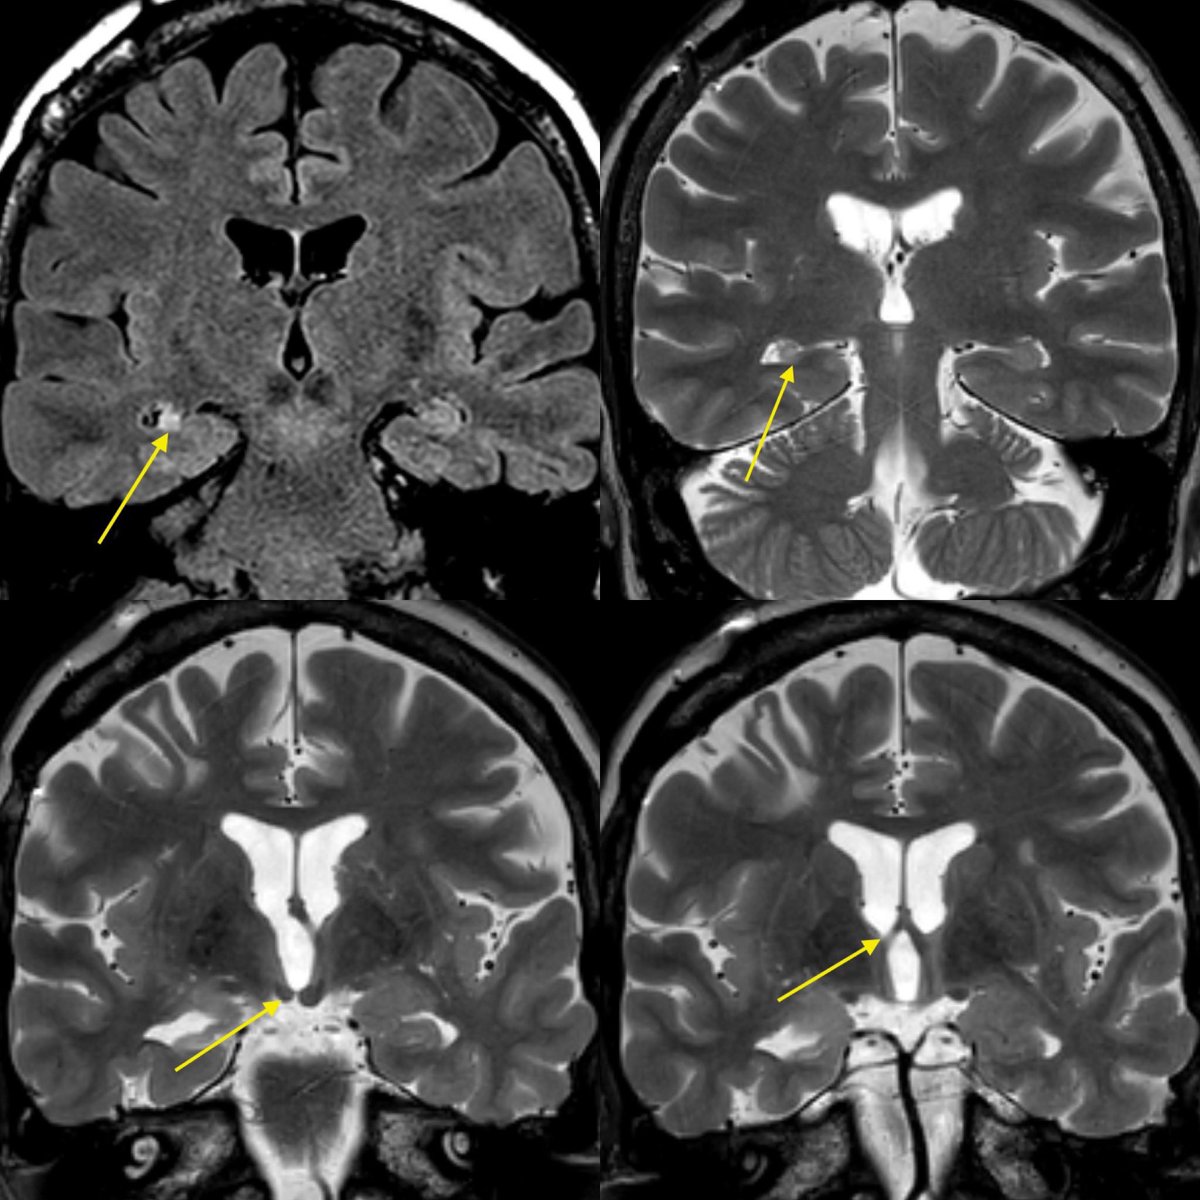

⭐️ Answer: Cortical vein thrombosis (CVT)